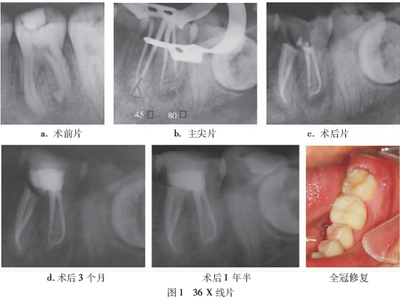

ROOT CANAL TREATMENT